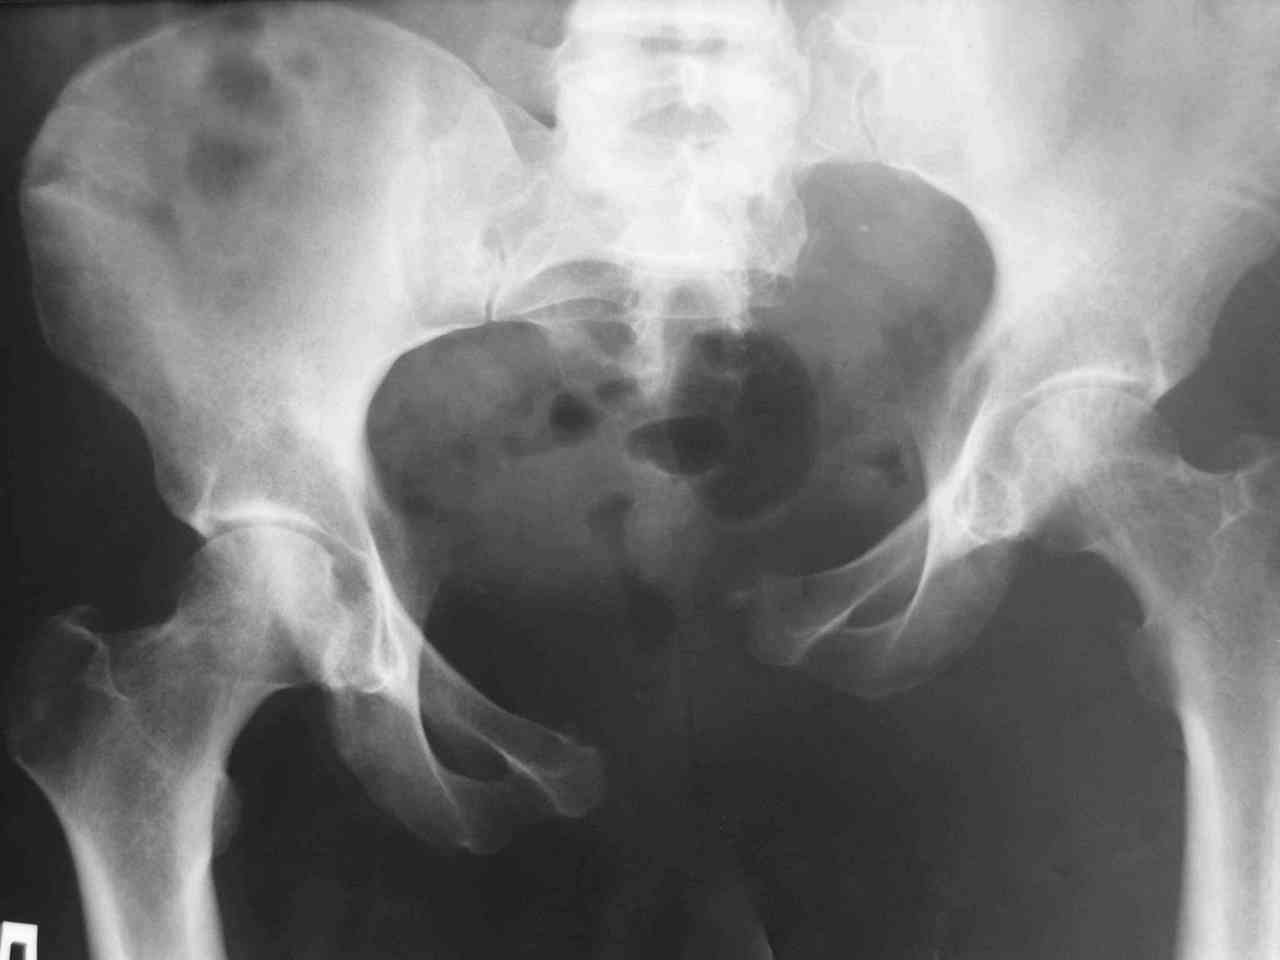

Пациентка получила травму таза 9 месяцев назад (перелом латеральной массы крестца слева, разрыв лонного сочленения).

Лечилась в стационаре другого города, без успеха. В мае 2007 прооперирована в нашем отделении, выполнена открытая репозиция повреждений, остеосинтез винтами латеральной массы крестца и пластинами лонного сочленения. Дополнительная фиксация аппаратом внешней фиксации. 3 недели спустя упала в палате на ягодицы, при этом получила повторную травму таза, смещение отломков. Уважаемые коллеги каково ваше мнение о способе фиксации полученных повреждений. С уважением Алексей.